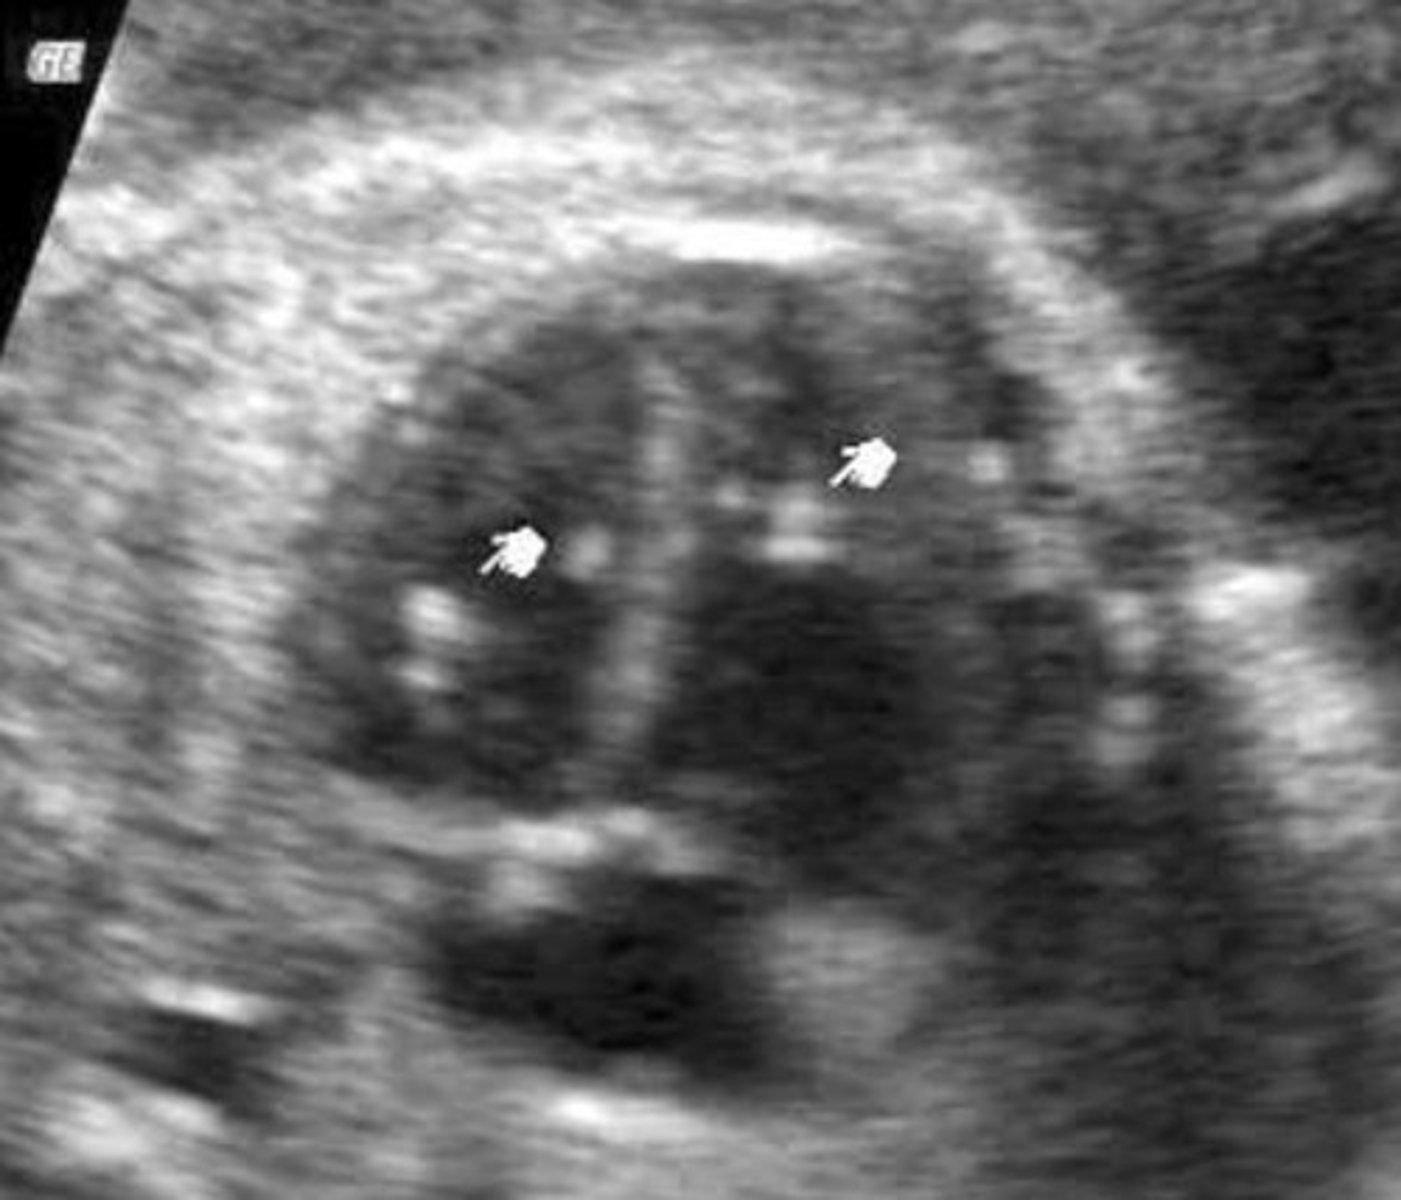

Choroid Plexus Cysts

Must be at least 2mm

Associated with Trisomy 18